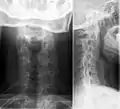

صورة بالأشعة السينية تظهر ضلع رقبي على الجانب الأيمن.